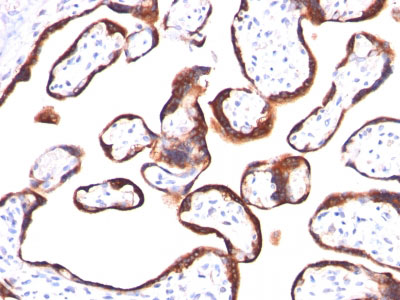

Formalin-fixed, paraffin-embedded human Placenta stained with hCG beta Monoclonal Antibody (HCGb/459). |